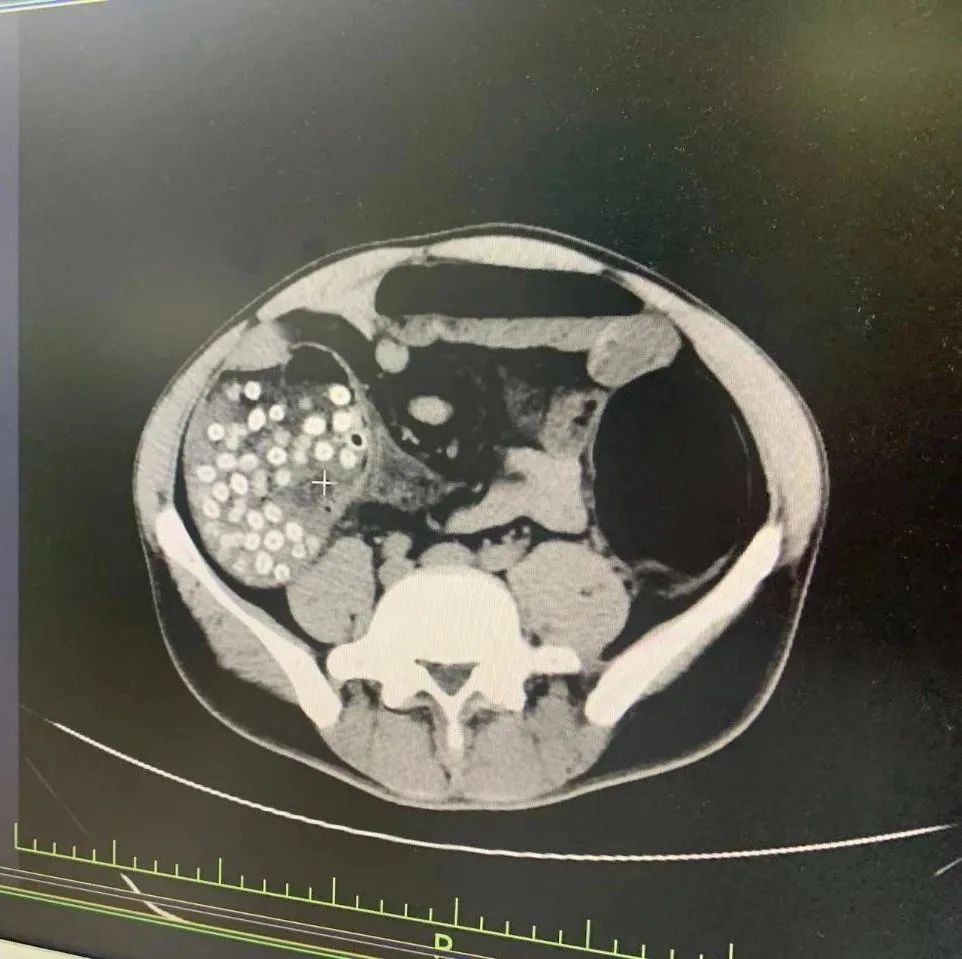

你听说过小肠结石肠梗阻吗

图片尺寸3968x2976